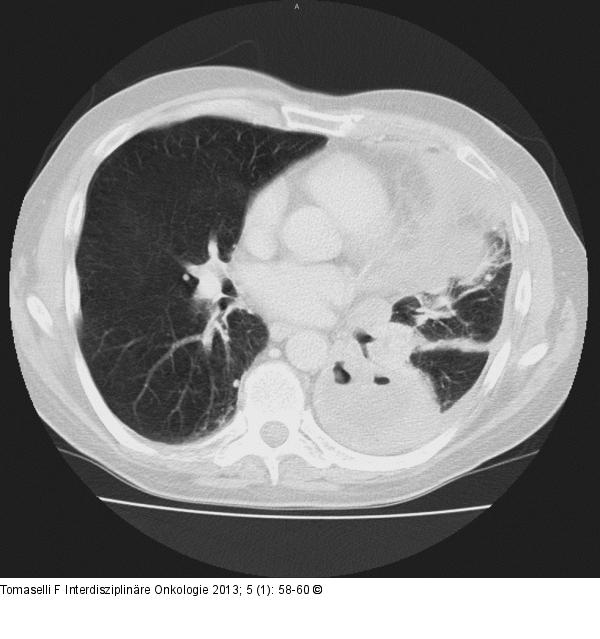

Abbildung 1: Thorax-CT Präoperatives Thorax-CT bei therapierefraktärer Stenoseproblematik cT2-3cN2cM1 (cereb.) |

Abbildung 1: Thorax-CT

Präoperatives Thorax-CT bei therapierefraktärer Stenoseproblematik cT2-3cN2cM1 (cereb.) |